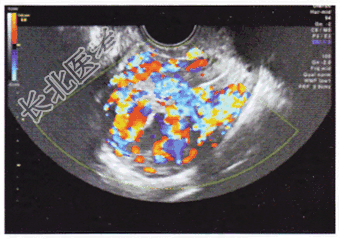

- 单项选择题患者,女, 29岁,足月产后1年, 阴道不规则流血伴腹痛2个月,血HCG滴度为21×104U/L。超声检查如图所示。最可能的诊断是

A、妊娠组织残留物

B、胎盘部位滋养细胞疾病

C、绒毛膜癌

D、局灶性子宫腺肌症

E、局部肌层血管畸形